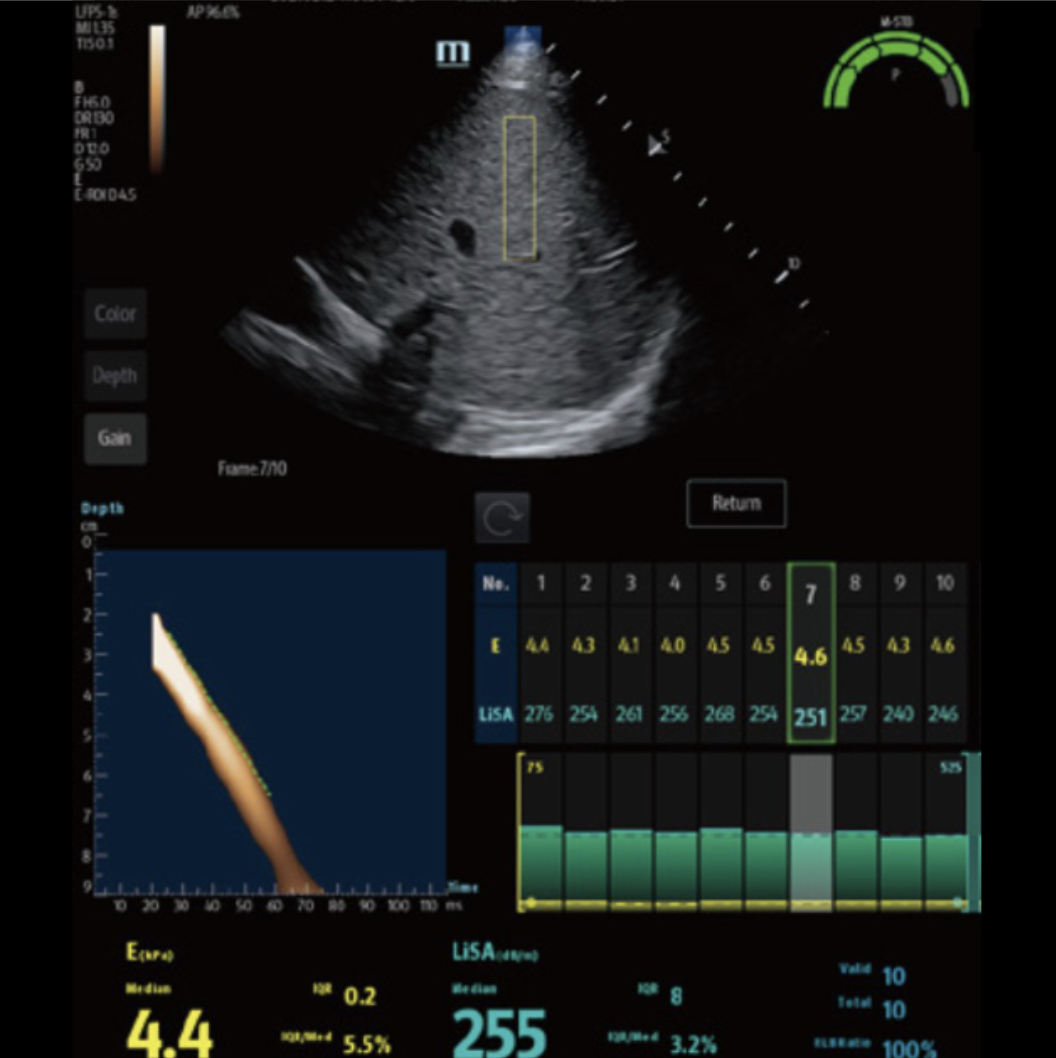

Hepatus

Hepatus is an imaging-based test developed by Mindray that combines regular ultrasound pictures with a method called transient elastography to measure liver steatosis and fibrosis. A Hepatus scan is quick and results can be ready in seconds once the probe is placed on your skin. The output gives two numbers: one showing how much fat is in the liver, and another showing how stiff it is. These numbers help your doctor decide if you have liver disease, how advanced it may be, and how it should be monitored over time.

The Hepatus scan also creates clear images of the liver that help doctors look for signs of disease. These images can show changes in the liver tissue, possible signs of liver cancer (HCC), and fluid buildup in the belly (ascites). The test can also check blood flow in the liver’s main vein, called the portal vein. This helps doctors see if blood is moving normally or if there are signs of portal hypertension, which is high pressure in the liver’s blood vessels.